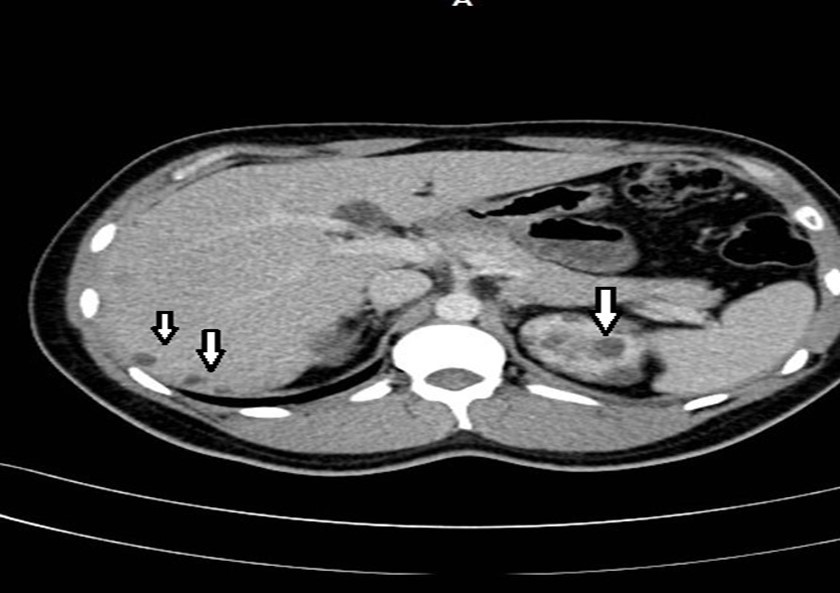

33-year-old male, son of the woman from case 1, with diagnosis of polycystic kidney and liver disease (Figure 3, Figure 4) since 29 years old , with normal liver and kidney function; At that moment general measures were started based on a diet low in sodium, increasing the consumption of natural liquids, avoiding nephrotoxic drugs and monitoring blood pressure.

At physical examination, without alterations. The abdominal thomography reports kidneys in habitual anatomical projection with loss of their morphology and increased sizes with loss of the sinus parenchyma relationship due to cystic-looking structures; right kidney with dimensions 14.3x 8.9 x 6.6 cm left kidney 17.3 x 11.6 x 8.2 cm in its longitudinal, transverse and anteroposterior diameters respectively, poorly determined echogenic renal sinuses, the left renal sinus with solid oval shades measuring 0.6 to 0.8cm on average and some calcifications; liver ultrasound showed cystic lesions. Laboratory creatinine 0.96mg/dl, urea 31.03 mg/dl

Figure 4.Contrast CT shows non complicated small liver cysts and multiple renal cysts.